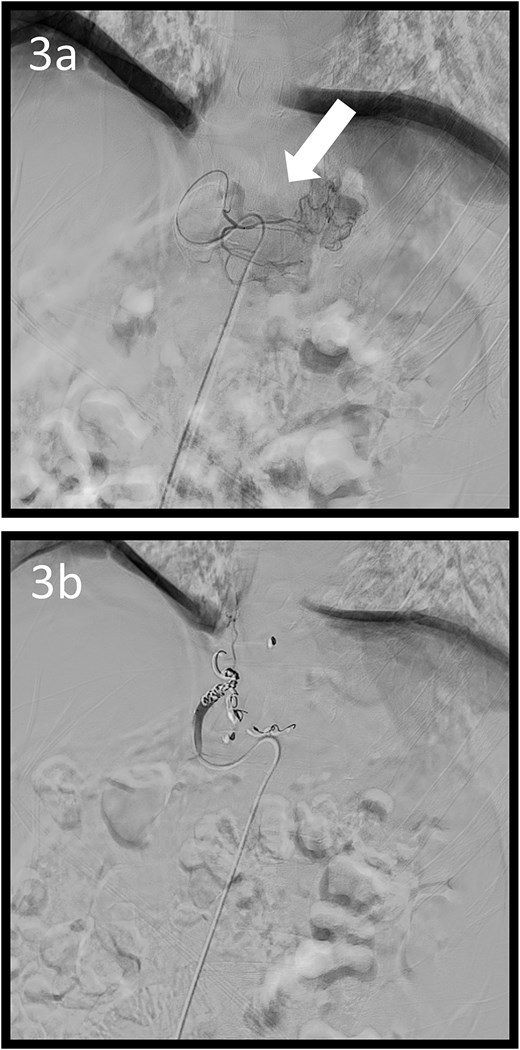

Angiographic images; (a) the left gastric arteriography showing tumour staining (arrow); (b) the left gastric artery was coil embolized.